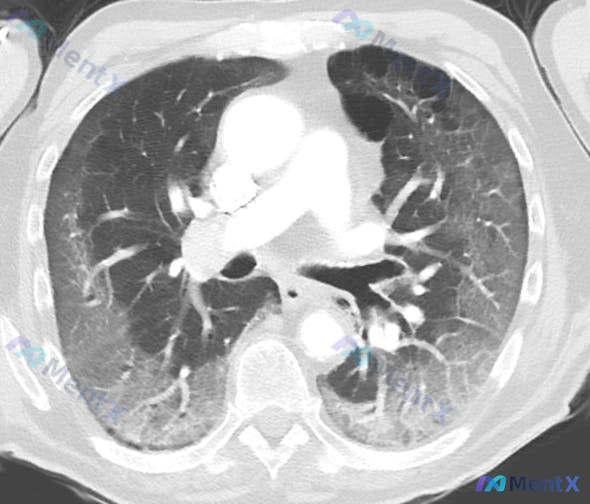

看到这个病例,整理了一下资料和思路,分享给大家一起讨论。 病例基本信息 - 患者:63岁男性 - 主诉:夜间呼吸困难,睡眠时「窒息感」,同时伴劳累后疲劳、呼吸困难 - 体格检查:S1正常,P2响亮,颈围43cm(正常<35cm),体温37℃,血压128/82mmHg,脉搏86次/分,呼吸19次/分...